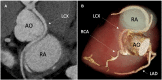

Case summary: We describe a 34-year-old man with a history of a single episode of chest pain. An ectopic origin on the part of the left circumflex (LCX) coronary artery from the proximal right coronary artery (RCA) was evident upon coronary computed tomography angiography. A positron emission tomography perfusion study revealed a stress-induced perfusion defect in the anomalous LCX territory (infero-posterior wall). The patient experienced dyspnoea and ST-segment depression in electrocardiography, suggestive of myocardial ischaemia during the maximal bicycle ergometer stress test. No mechanical compression or stenosis was seen upon invasive coronary angiography. The left ventricular perfusion normalized after the initiation of beta-blocker medication.